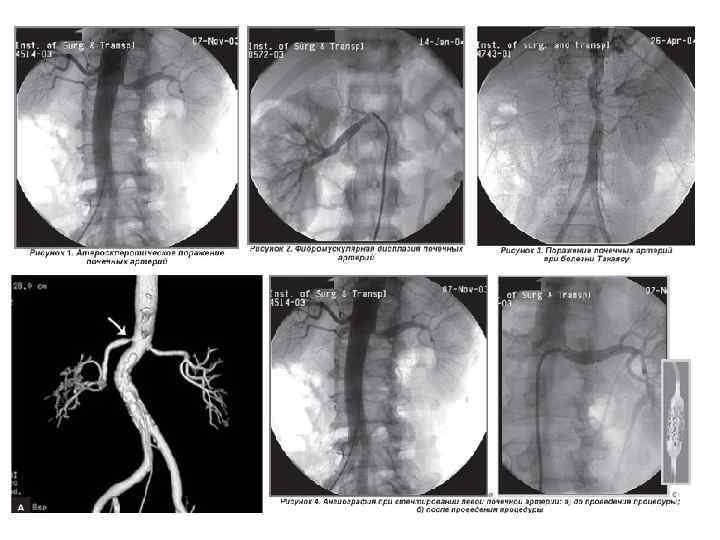

Синдром вазоренальной гипертензии Атеросклеротическое поражение почечных артерий • • • около 70% реноваскулярных гипертензий факторы риска атеросклероза, гиперхолестеринемия, клиника атеросклеротического поражения других артерий в 50 % выслушивается продолжительный систолический или систолодиастолический шум в проекции почечных артерий инструментальная диагностика: изотопная ренография (ангионефросцинтиграфия), экскреторная урография, компьютерная томография, брюшная аортография, катетеризация почечных вен (повышение содержания ренина в венозной крови пораженной почки) Лечение хирургическое - баллонная ангиопластика, хирургическая коррекция стеноза, нефрэктомия. Фиброзно-мышечная дисплазия почечных артерий • 10— 20% реноваскулярных гипертензий у женщин встречается в 4— 5 раз чаще, чем у мужчин чаще врожденная патология, АГ обычно развивается в молодом возрасте (до 40 лет). при ангиографии стенозы почечных артерий имеют вид нитки бус или жемчуга. • (панартериит, болезнь отсутствия пульса, синдром Такаясу) стенозирование аорты и магистральных артерий с ишемией пораженного органа. • • • Неспецифический аортоартериит

Синдром вазоренальной гипертензии Атеросклеротическое поражение почечных артерий • • • около 70% реноваскулярных гипертензий факторы риска атеросклероза, гиперхолестеринемия, клиника атеросклеротического поражения других артерий в 50 % выслушивается продолжительный систолический или систолодиастолический шум в проекции почечных артерий инструментальная диагностика: изотопная ренография (ангионефросцинтиграфия), экскреторная урография, компьютерная томография, брюшная аортография, катетеризация почечных вен (повышение содержания ренина в венозной крови пораженной почки) Лечение хирургическое - баллонная ангиопластика, хирургическая коррекция стеноза, нефрэктомия. Фиброзно-мышечная дисплазия почечных артерий • 10— 20% реноваскулярных гипертензий у женщин встречается в 4— 5 раз чаще, чем у мужчин чаще врожденная патология, АГ обычно развивается в молодом возрасте (до 40 лет). при ангиографии стенозы почечных артерий имеют вид нитки бус или жемчуга. • (панартериит, болезнь отсутствия пульса, синдром Такаясу) стенозирование аорты и магистральных артерий с ишемией пораженного органа. • • • Неспецифический аортоартериит